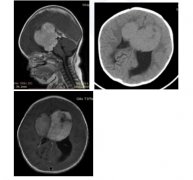

10个月婴儿患中脑顶盖胶质瘤,顺利全切肿瘤后恢复良好

这个女婴在2个月大时,在常规的临床检查中发现眼窝额...